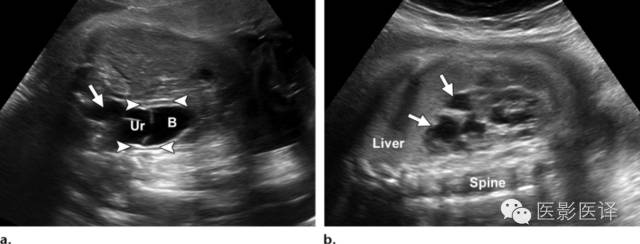

图11.输尿管囊肿及输尿管积水。(a)通过胎儿盆腔的超声斜横断面图像显示膀胱(B)内由输尿管囊肿(Ur)引起的“膀胱内膀胱”的征象。关注由此引起的输尿管积水(箭)。箭头指示脐动脉绕过膀胱,(b)同一胎儿,通过右肾的超声冠状面图像显示明显的肾盏扩张(箭)和被阻塞的上半部分肾皮质变薄。